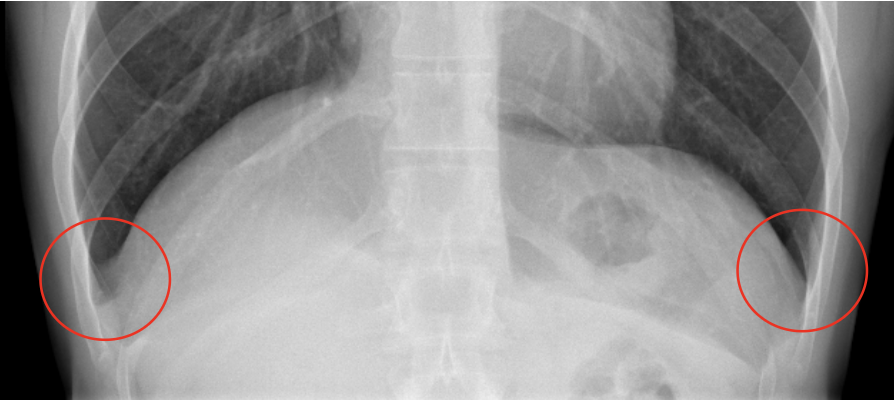

Pathology?

Pleural effusion (fluid in pleural space)